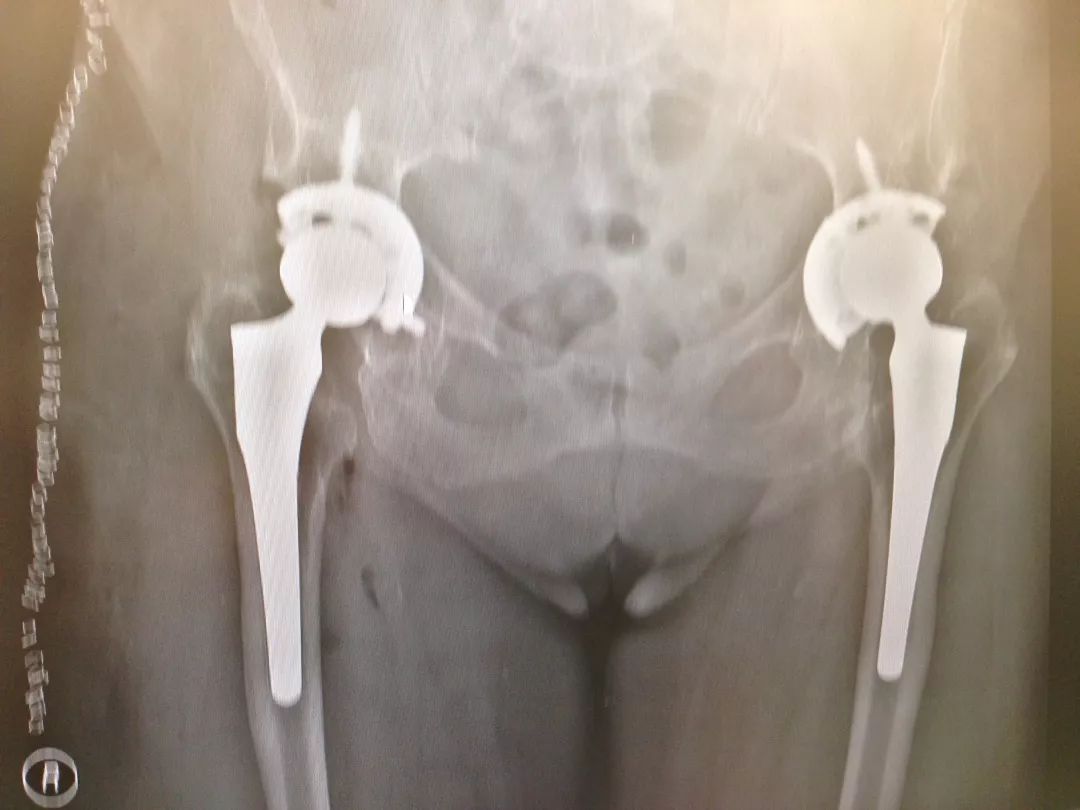

图1,75岁,女性患者,23年前因“双髋发育不良并骨关节炎”行双侧全髋关节置换术,术后恢复良好;右侧内衬磨损,行右侧髋关节翻修术(更换内衬和股骨头);左髋无痛,功能可。